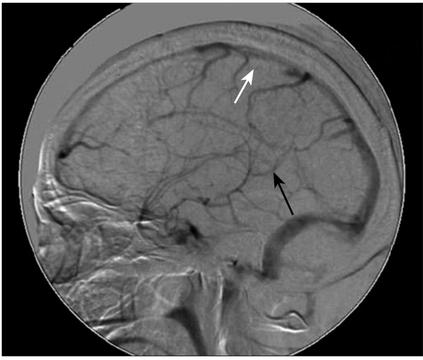

检查回报:血清铁蛋白(肿瘤标志物之一)360μg/L,升高。腰穿提示脑脊液压力>330mmH2O,细胞总数4个/μl,白细胞数2个/μl,糖正常,氯化物111mmol/L,降低,蛋白120mg/dl,升高。细胞学检测可见散在异形大细胞,可疑肿瘤细胞。颅脑磁共振(2007年7月4日)平扫提示脑实质未见异常,幕上脑室略扩大,增强后提示部分脑膜强化,静脉相提示上矢状窦末端及直窦血管粗细不均,似有部分血栓(图2)。经DSA(2007年7月12日)证实下矢状窦、直窦未显影,上矢状窦中段显影差,考虑静脉窦血栓形成(图3)。

图3 颅脑血管造影:下矢状窦、直窦未显影(黑箭头),上矢状窦中段显影差(白箭头)